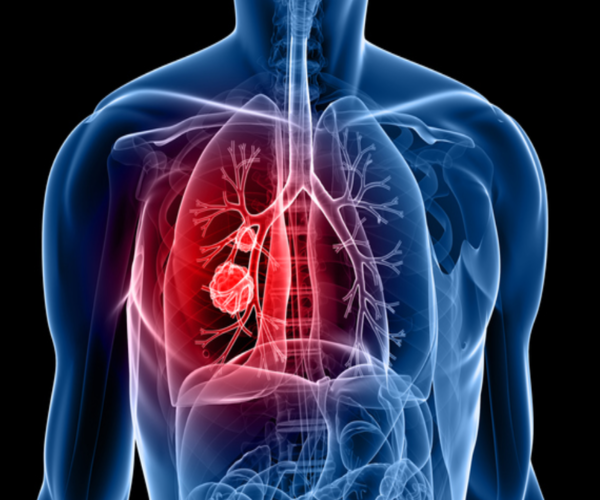

폐암 초기증상 11가지

1. 가슴 통증

폐암 환자의 30% 이상이 가슴 통증을 호소하더라고요. 초기에는 날카로운 통증이, 진행이 되면 크고 무거운 통증이 느껴질 수 있고요. 이런 증상을 보이는 경우에는 다짜고짜 병원을 방문해서 검사를 받아보시기 기도하더라고요

2. 호흡 곤란

폐암 환자의 반절 크기가 숨이 차다고 느낍니다. 암 덩이가 커져서 호흡이 가쁘다고 인지하는 경우도 있겠지만, 폐암으로 인한 흉막삼출(가슴막삼출이라고도 하며 폐를 둘러싼 두 겹 흉막 사이의 좁은 공간에 흉수라고 불러내는 삼출액이 차는 현상)이나 폐허탈(종양이 기관지를 막거나 흉수가 차는 바람에 폐포의 공기가 급속히 빠져나가 폐가 짜부러지는 것), 상기도 폐색 등이 호흡곤란을 유발하기도하더라고요.

9. 기침

폐암 초기증상 중가장 수시로 보이는 것이기도 하며 폐암 환자의 50~75%가 겪는 증상으로 기침이 한 달 이상 연속된다면 폐암에 대한 검진을 받아보셔야하더라고요. 폐암의 주원인은 흡연이라고 합니다. 폐암 까닭의 약 90%를 구성하는 것으로 추측되고 있는있다는데, 흡연자는 비흡연자보다 폐암에 걸릴 위험이 15 ~ 80배나 높다고 합니다.흡연자분들은 건강을 위해 CT촬영, 흉부 엑스레이 등의 검진을 주기적으로 받는 것을 권고드립니다 하겠습니다.